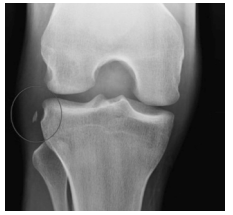

Um paciente de 22 anos de idade realizou torção de joelho direito jogando futebol há um dia. Apresenta-se com edema articular importante, o que impede a realização apropriada das manobras do exame físico. Joelho difusamente doloroso à palpação.

Com base no caso clínico apresentado e na imagem de radiografia, é correto afirmar que se trata de uma fratura de